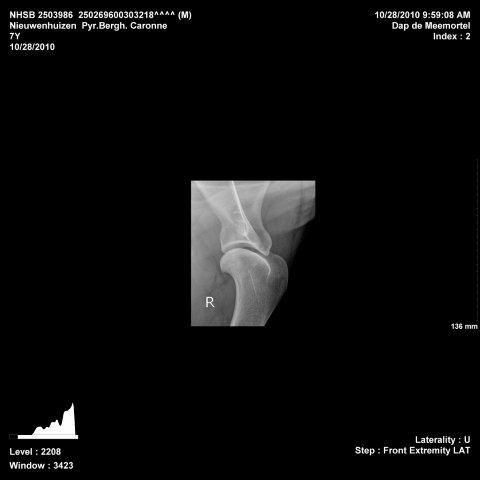

28-10-2010 After our Caitlin is also Caronne checked on OCD and ED and also these X-rays look perfect! Here under the X-rays, 1 of each shoulder to check on OCD and 2 of each elbow to check on OCD and ED

24-10-2009 Today our Cath "deserved" her first VG on the show in Utrecht, Netherlands. Judge: R. Chiodi-Walraven (NL). Pyrenean Mountain Dogs present: 12, 5 males and 7 females